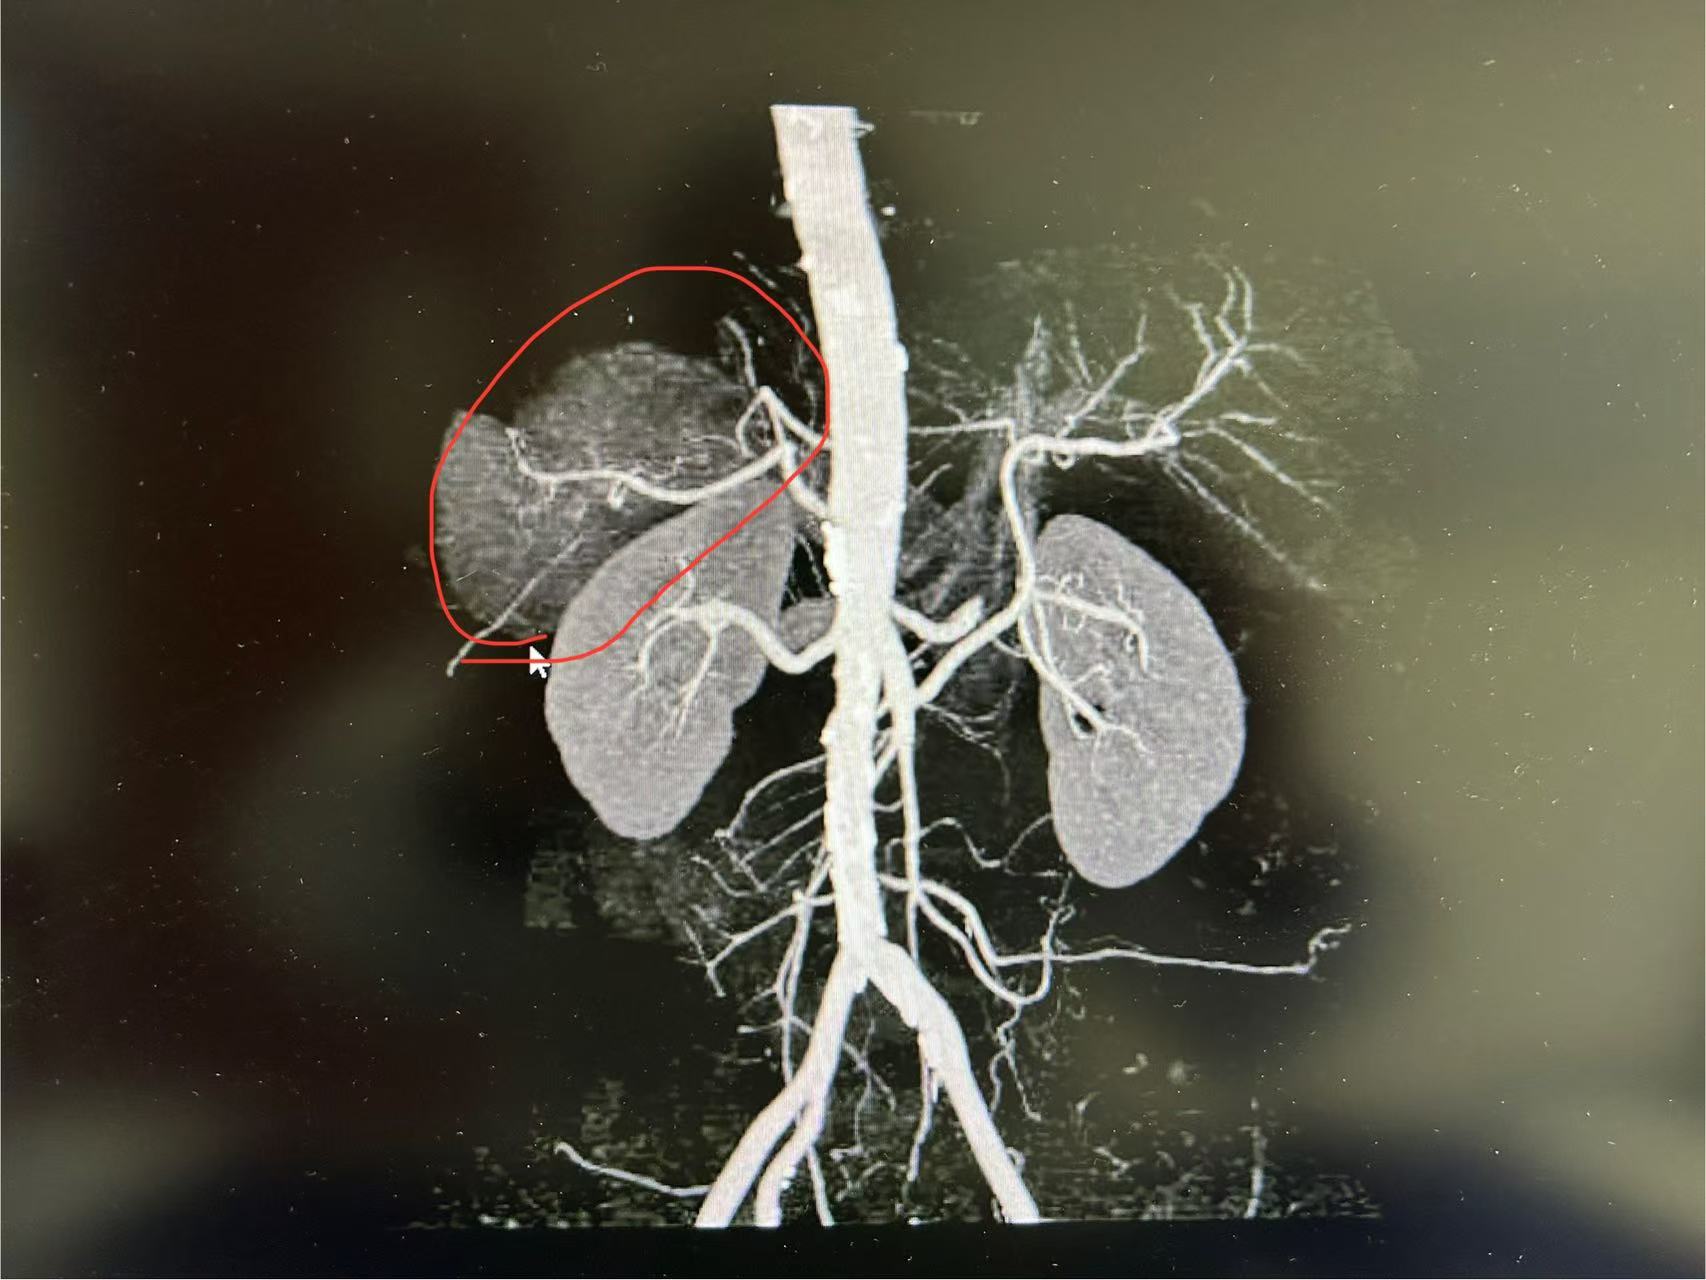

一般超过7CM的错构瘤多采取开放手术切除,该患者肿瘤超过9CM,邱教授建议采用后腹腔镜手术切除,为了能在安全切除肿瘤的同时保住肾脏,邱云桥教授团队对患者CT影像学信息进行了肾脏及血管三维重建。

据邱云桥教授介绍,郑女士的肿瘤在肾上极包绕肾动脉、静脉,而且还向外压迫下腔静脉、肠管、肝脏和胆囊。手术风险很大,稍有不慎就会造成血管损伤大出血、丧失肾脏和损伤周围重要脏器等严重并发症。